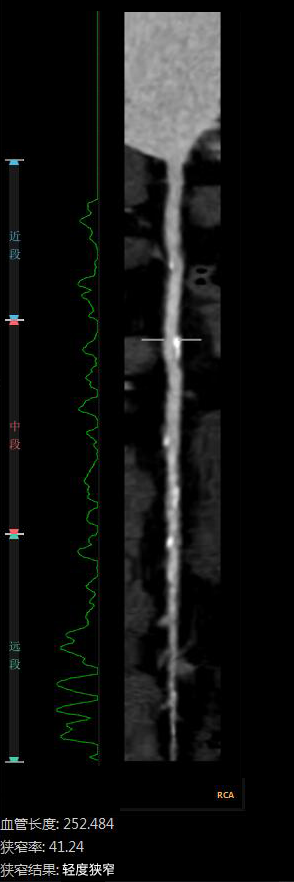

“CTA冠脈全自動(dòng)診斷”

Automatic Coronary Diagnosis

全自動(dòng)圖像重建/分割

全自動(dòng)量化測量

云端AI的CTA冠狀動(dòng)脈全自動(dòng)診斷

重構了CTA冠脈檢查的極簡(jiǎn)流程